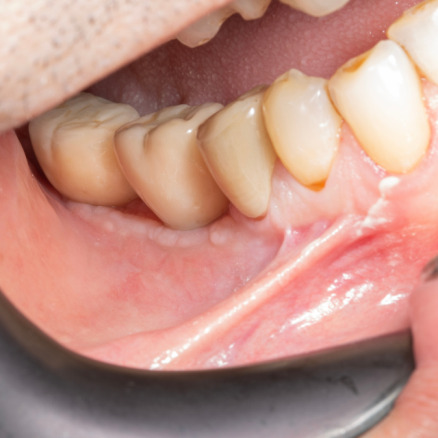

İmplant etrafındaki kemik açıklığını kemik grefti ile tedavi ettiğimiz vakamızdan biri